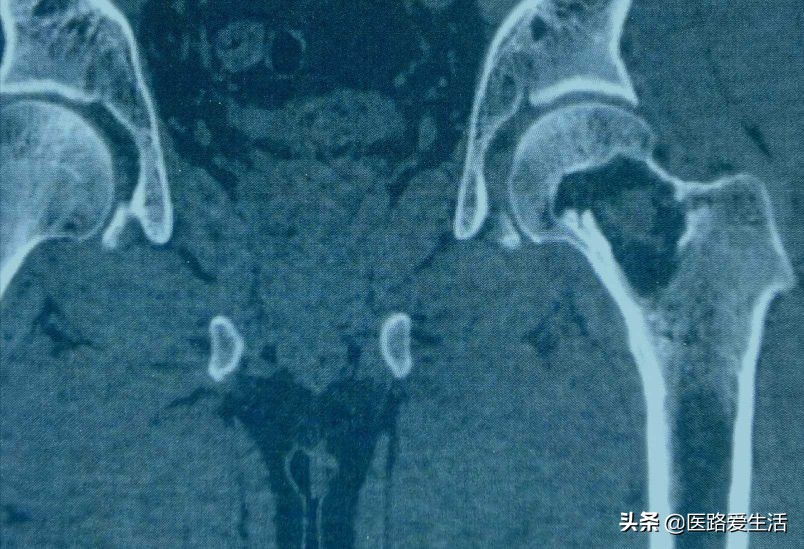

2.还有CT可提示病变的横断面影像。